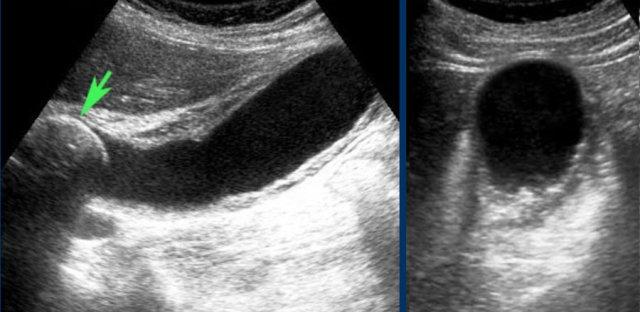

Ở tư thế nằm ngửa, một viên sỏi (mũi tên) được phát hiện tại cổ túi mật.

Sau khi đứng dậy, cúi người và đi lại, viên sỏi (mũi tên) không di chuyển xuống, do đó phải là sỏi kẹt.

Sỏi trong ống túi mật đôi khi không thể hiển thị được trên mặt phẳng siêu âm theo trục dọc của túi mật.

Hình ảnh của một bệnh nhân bị phình to túi mật cấp tính do sỏi kẹt.

Sỏi kẹt không thể hiển thị được trên trục dọc của túi mật, do vị trí nằm ở phía trong của ống túi mật (mũi tên).